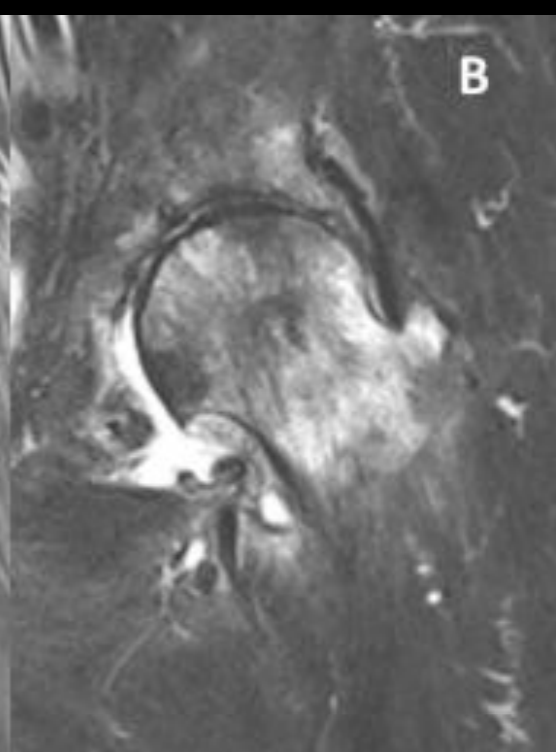

RM pinzamienro femoroacetabular

A

Edema óseo hiperintenso

Pinzamiento leve

Lesión del labrum